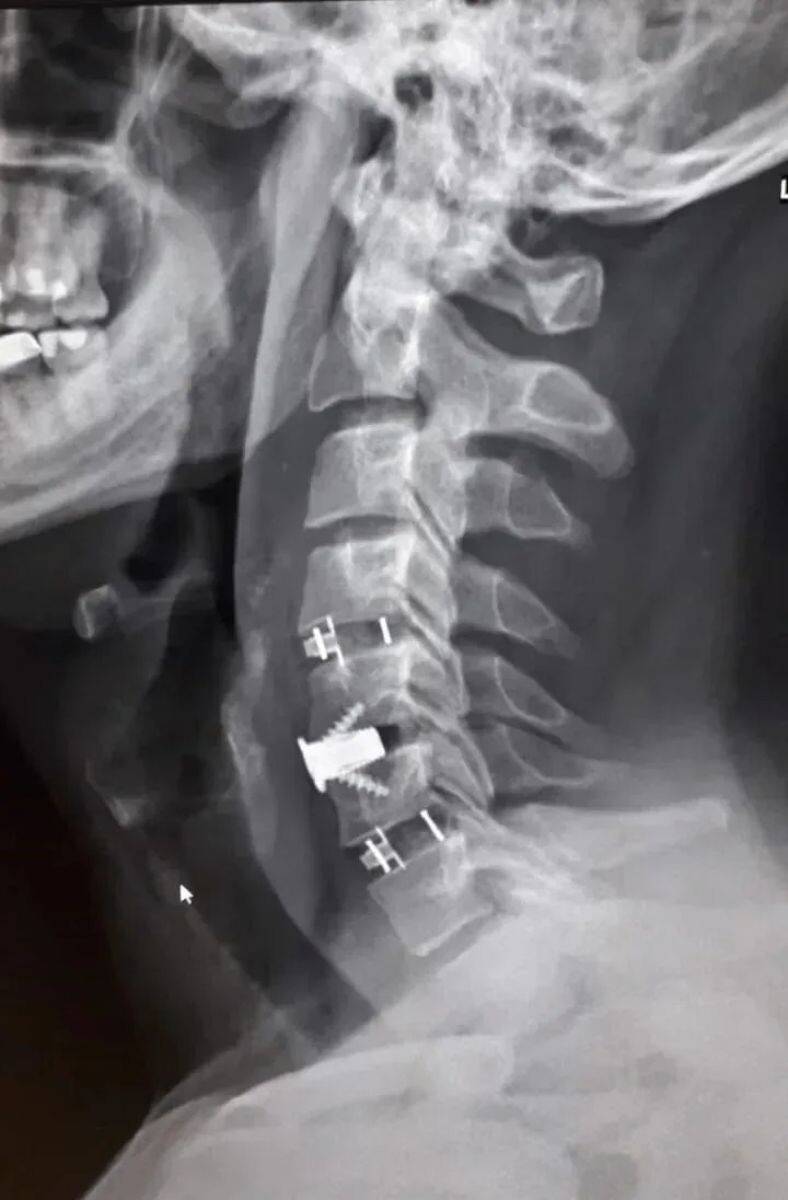

Нейрохирурги Воронежской городской клинической больницы скорой медицинской помощи №1 (БСМП №1) провели уникальную операцию 38-летнему пациенту, полностью восстановив ему свободу движений в руках. Команда под руководством заведующего отделением Павла Юрова устранила стеноз позвоночного канала, стабилизировала и укрепила шейный отдел титановыми конструкциями. Об этом сообщили в пресс-службе министерства здравоохранения Воронежской области 30 марта.

Мужчина годами мучился от остеохондроза шейного отдела. С августа 2025-го боль усилилась, распространилась на правую руку, добавив слабость и онемение. В стационаре мужчине поставили диагноз – диско-остеофитный стеноз позвоночного канала.

Результат операции впечатляет: уже через 3 часа пациент встал на ноги, не испытывал боли, а силы вернулись в мышцы. Мужчину выписали на 5-е сутки, но впереди его ждет реабилитация.